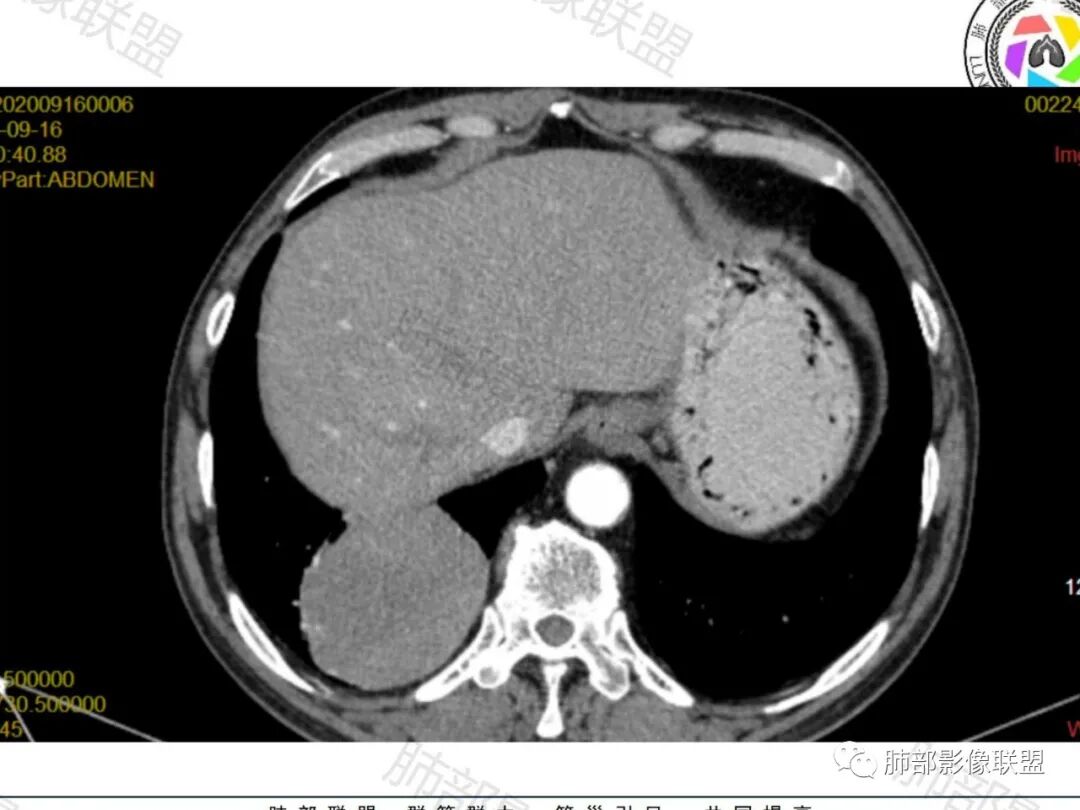

老年男性,肿瘤标志物高,右肺下叶类圆形肿块,宽基底与胸膜相连,边缘光整,密度均匀,周围气管及血管受压推移,延迟强化,其内见纤细血管,似有小低密度灶,首先考虑间叶组织恶性肿瘤,良性平滑肌瘤、纤维瘤不除外

患者中老年男性,检查发现右下肺占位。查肺癌标记物稍有升高。血常规白细胞计数稍降低。胸部CT:右肺下叶后基底段类圆形肿块,边缘光滑,边界清楚,周边见气管受压扩张,增强轻度强化,内见点状低密度影,见血管贴边。综合考虑良性过低度恶性病变,PSP可能,其它恶性肿瘤待排。

老年男性,右肺下叶软组织肿块,边缘光滑,血管和支气管贴边,肿块与膈肌分界不清,增强后不均匀强化,可见点片状低密度影,考虑良性或低度恶性肿瘤,psp,神经内分泌肿瘤

右肺下叶大肿块,血管贴边,部分小分支进入肿块内,密度略欠均匀,边缘总体光滑,支气管关系不明确,老年人,总体考虑恶性,nse高,首先考虑神经内分泌癌,鉴别肉瘤,转移瘤

右下肺大团块,边界较清,病灶内有血管影,小灶低密度,胸膜下脂肪清晰,需要薄层确定肺血管有没穿行,疾病谱:神经内分泌癌(大 类),SFT,PSP,肉瘤样癌,间叶肿瘤,考虑神经内分泌癌(大 类)>sft>psp>肉瘤样癌

老年男性,检查发现右下肺占位。CT:右肺下叶一类圆形肿块影,膨隆,无分叶,边缘基本光滑,近端支气管推挤狭窄,与胸膜夹角为锐角,增强见不均匀强化,未见坏死,近端见血管贴边,胸壁脂肪间隙清楚。考虑良性病变——PSP可能性大。鉴别神经内分泌癌、肉瘤、SFT。

右肺下叶软组织肿块,边缘光滑,临近血管受压变形且增粗,增强后见斑片状低强化区,界不清,实性部分见条状血管影,边缘光滑,考虑PSP可能,肿块与支气管关系不密切,腺癌,腺鳞癌不符合,肿块内增强后血管走形自然,间叶组织起源肉瘤不符

右肺下叶肿块,呈外带大内带小的椭圆形改变(内带受支气管及血管挤压原因),边缘光滑,无分叶毛刺,支气管受压,增强后,均匀延迟强化,动脉期见血管贴边,静脉期内部瘤样血管强化区,相邻胸膜无侵犯,纵隔无淋巴结肿大,符合PSP,不鉴别。

老年男性,右肺下叶肿块,边界光滑,血管贴边,部分小分支进入,肿块内可见增粗血管,肿瘤指标偏高,总体考虑恶性,不典型类癌?大细胞癌?鉴别PSP。

胸部CT:右肺下叶一类圆形肿块影,边界清楚,大部分边缘光滑、外缘边界模糊,邻近支气管推移、血管贴边,病灶内可见分枝状血管,平扫密度尚均匀,增强后大部分均匀延迟强化,部分与膈肌黏连、尾征?考虑:类Ca>PSP>SFT。鉴别肉瘤样Ca,CD等。

肿块位于周围(起自细支气管呼吸道上皮),均匀膨胀生长(符合良性的生长特点),病灶内部大部分密度较均匀,部分小低密度不强化区(囊变),增强强化较明显,边缘血管增粗贴边,临近支气管受压,支持PSP。